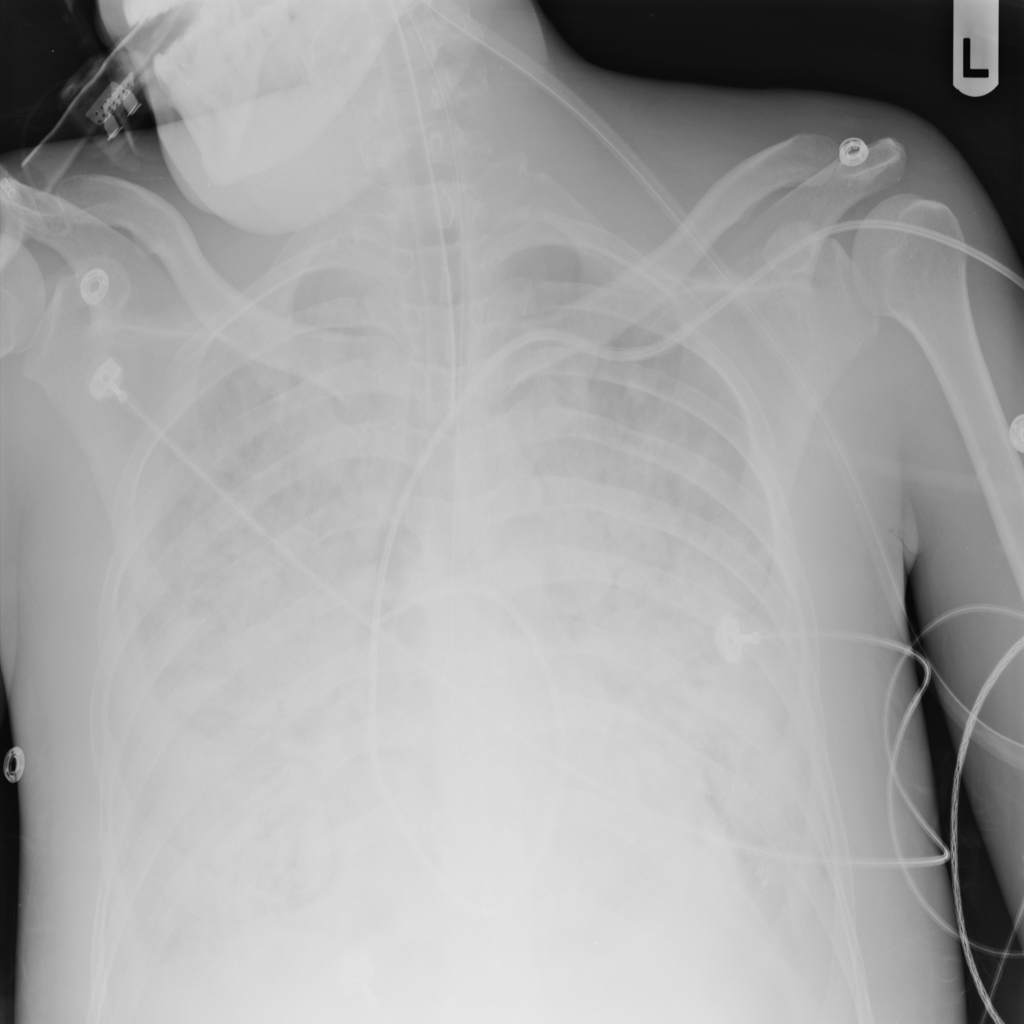

PAT-5B86 · IMG-009Edema

PAT-5B86 · IMG-009

PA